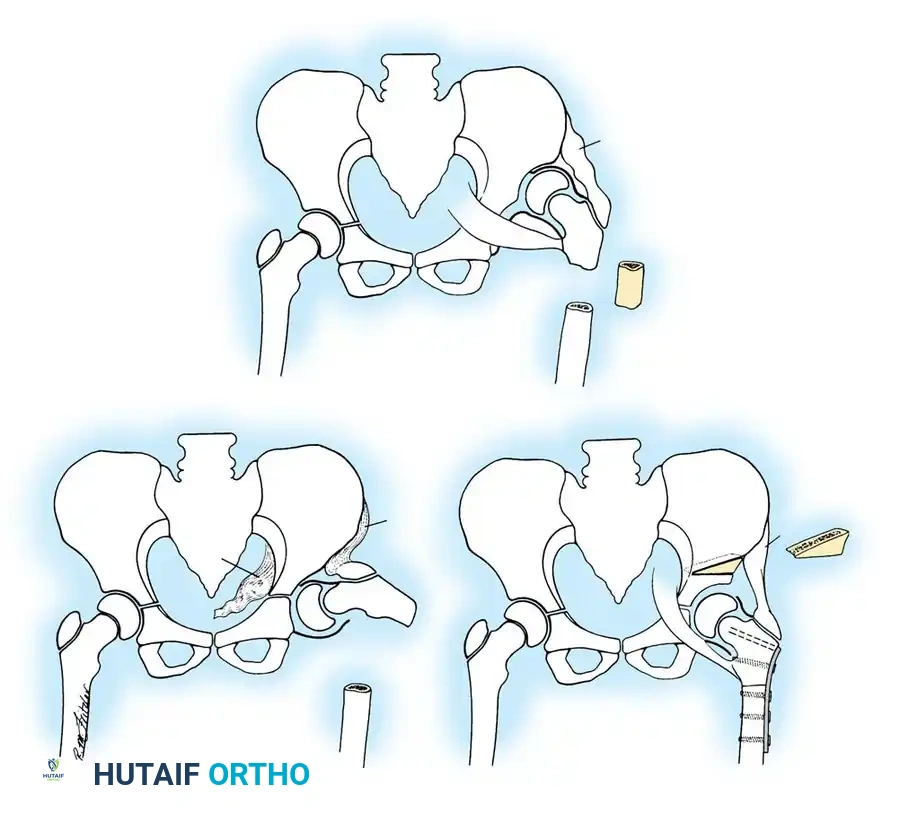

Pelvic Osteotomies:

Pelvic osteotomies are broadly categorized into redirectional (e.g., Salter, Triple) and reshaping/volume-reducing (e.g., Pemberton, Dega).

- Salter Innominate Osteotomy:

- Indications: Children aged 18 months to 6 years with a congruous joint but anterolateral acetabular deficiency.

- Biomechanics: A complete transverse cut is made through the ilium just above the acetabulum to the sciatic notch. The entire acetabulum is rotated anteriorly and laterally, hinging on the pubic symphysis.

- Fixation: A triangular bone graft (harvested from the iliac crest) is placed in the osteotomy site, and the construct is stabilized with threaded Kirschner wires.

Diagrammatic representation of the Salter Innominate Osteotomy. Note the complete iliac cut and the placement of the triangular bone graft to redirect the acetabulum.

- Pemberton Pericapsular Osteotomy:

- Indications: Severe dysplasia with a capacious acetabulum.

- Biomechanics: An incomplete cut is made through the ilium, curving down to the triradiate cartilage, which acts as a hinge. This reshapes the acetabular roof, reducing its volume and improving anterolateral coverage.